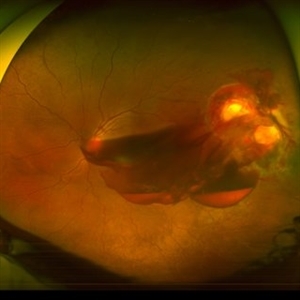

Wyburn Mason Racemose Angiomatosis

Color fundus montage of an 13-year-old female with arteriovenous malformation (Wyburn Mason Racemose Angiomatosis) affecting her right eye. The retinal arteriovenous malformation appears to be stable. She presented with NLP in the eye, strabismus, and peripheral retinal ischemia. She is at risk for neovascular complications; however, she is currently being treated with Sirolimus. Since she is on this systemically, there is no need to perform intraocular anti-VEGF injections or PRP laser. She also presented with optic atrophy affecting her left eye, secondary to chiasmal involvement of arteriovenous malformation. She has had a potential progressive visual field loss involving the temporal aspect of her visual field from the left eye. There is sector optic atrophy. Presumably, this is due to a compressive effect of her arteriovenous malformation on the nasal nerve fiber layer (corresponding to the temporal visual field) crossing to the right occipital cortex at the chiasm.

Photographer: Olivia Rainey

Imaging device: Topcon 50dx

Condition/keywords: arteriovenous malformation, color fundus photograph, color photo, montage, peripheral ischemia, Sirolimus